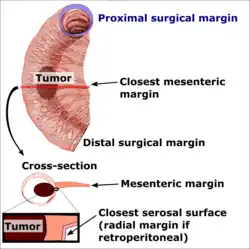

A resection margin or surgical margin is the edge or "margin" of apparently non-tumorous tissue around a tumor that has been surgically removed, called "resected", in surgical oncology. The resection is an attempt to remove a cancer tumor so that no portion of the malignant growth extends past the edges or margin of the removed tumor and surrounding tissue. These are retained after the surgery and examined microscopically by a pathologist to see if the margin is indeed free from tumor cells (called "negative"). If cancerous cells are found at the edges (called "positive") the operation is much less likely to achieve the desired results.[1]: sections 1-2

The size of the margin is an important issue in areas that are functionally important (i.e., large vessels like the aorta or vital organs) or in areas for which the extent of surgery is minimized due to aesthetic concerns (i.e., melanoma of the face or squamous cell carcinoma of the penis).[2] The desired size of margin around the tumour can vary. In resections for breast cancer, there appears to be a difference between European and American radiation oncologists, with the former preferring larger margins of over 5 mm.[1]: section 2

The Margin Status following tumour resection (AJCC 8th Edition):

- Negative margin: No tumour at the margin.

- Microscopic positive margin: Tumour identified microscopically at the margin.

- Macroscopic positive margin: Tumour identified grossly at the margin.

- Margin not assessed.

Surgical margin in a surgery report defines the visible margin or free edge of "normal" tissue seen by the surgeon with the naked eye. Surgical margin as read in a pathology report defines the histological measurement of normal or unaffected tissue surrounding the visible tumor under a microscope on a glass mounted histology section.[4][5] A "narrow" surgical margin implies that the tumor exists very close to the surgical margin, and a "wide" surgical margin implies the tumor exists far from the cut edge or the surgical margin. Narrow surgical margin using the bread loafing technique suggests that residual cancer might be left due to false negative error. A surgeon often will perform a second surgery if a narrow surgical margin is noted on a pathology report.